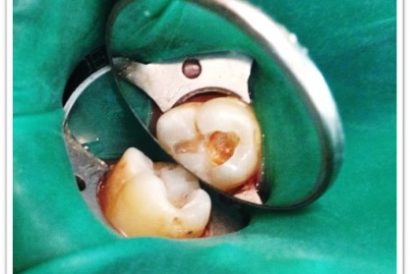

Patient Name:Akshay Gharat

Tooth Involved :16

Diagnosis :Caries Involving Enamel And Dentin Mesiocclusally

Treatment :Class Two Direct Composite Restoration Using Nanohybrid Composite

Before